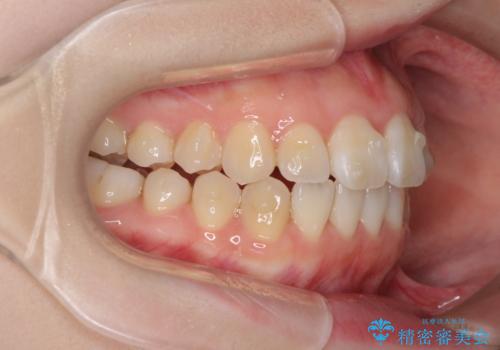

- 前歯の捻れと、ちょっとした出っ張りを気にして来院された患者様です。

歯と歯の間を削る(IPR)ことでデコボコを解消し、インビザラインで整えることとしました。

インビザライン治療特有の奥歯が接触しない時期が続き、当初予定よりも期間がかかりましたが、最終的には安定した咬み合わせと、整った前歯になりました。